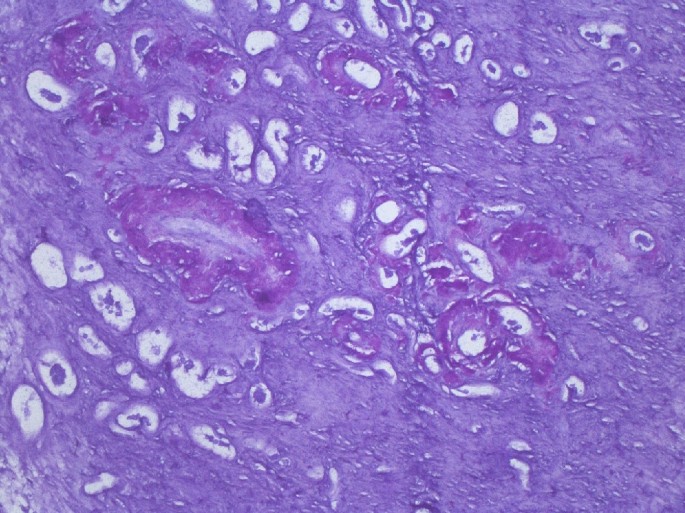

When the patient returned to our department, she had bicytopenia (anemia + thrombocytopenia, renal failure (blood urea nitrogen [BUN]: 76.3 mg/dL, creatinine [Cr]: 7.54 mg/dL) and metabolic acidosis. She underwent haemodialysis and received ES transfusion. Both protein electrophoresis and PNH panel were normal. In the PET-CT image, the spleen was extremely enlarged, and a diffuse increase was noted in gastric wall [standardized uptake value (SUVmax): 10.8]. In the endoscopic examination, diffuse hyperaemia and oedema were seen along the mucosa and walls of the gastric corpus and antrum. Samples were collected for a gastric biopsy which resulted as AA amyloidosis and chronic gastritis. Daily 2–3 units of ES transfusion were required to manage severe menometrorrhagia of the patient. In our opinion, thrombocytopenia was caused by hypersplenism, and anemia was induced by bleeding and hypersplenism. Provisional diagnoses of amyloidosis-associated massive splenomegaly and hypersplenism were made, and splenectomy was decided. Department of Gynecology initially employed hormone therapy for persistent menometrorrhagia without success. As bleeding worsened, surgery was decided. Prothrombin time, activated partial thromboplastin time, and international normalized ratio; fibrinogen, and factor VII, VIII, IX, XI, and XIII values of the patient were lying within their respective normal range, but platelet aggregation was disrupted as measured by ristocetin cofactor assay (RCof) (Factor X testing is not available in our site, therefore was not done). Thus, menometrorrhagia of the patient was attributed to platelet dysfunction and thrombocytopenia with a likely contribution of amyloidosis. The patient underwent splenectomy + hysterectomy and bilateral salpingo-oophorectomy in a single operating session. In the pathological examination, the left ovary and spleen were stained with crystal violet and Congo red which produced a staining pattern suggesting amyloids, and amyloid A staining was positive. Suspecting amyloid deposition also in the uterus, we applied uterine amyloid staining. Crystal violet staining was consistent with amyloid deposits at superficial myometrial vessel walls (Figs. 1, 2, 3). Moreover, amyloid deposits in patches were indicated at endometrial vessel walls. No postoperative complications were observed. Following the splenectomy, thrombocytopenia of the patient recovered. She was initiated on anakinra 100 mg/every other day subcutaneous for FMF-associated diffuse secondary amyloidosis. The patient had no active complaints in the postoperative 2nd month and 1.5 months after the anakinra treatment and the haemodialysis program was continued. The acute phase response and hemogram of the patient returned to normal completely. However, proteinuria was continued. (Clinical and laboratory findings of the patient are given in Table 1.)

Fig. 1

figure 1

Crystal violet staining suggesting amyloid deposits at superficial myometrial vessel walls (arrow). Endometrial glands are visible on the right (crystal violet × 200)

AA amyloidogenesis may take place at various layers of the uterus. While AA amyloidosis in RA patient was detected at perivascular regions of the endometrium, the case with AL amyloidosis was shown to have deposition at myometrial blood vessels [9, 13]. Amyloids were determined in the superficial myometrium and endometrium in our case. In the AL amyloidosis case described by Copeland et al., on the other hand, a broader involvement covering uterus, cervix, corpus, fallopian tubes, and ovaries as well as the appendix and omentum was mentioned [11]. AA amyloidosis secondary to tuberculosis involving adrenal glands, liver, and kidneys in addition to ovaries which is accompanied by calcification has been described in the literature. However, it was not clarified whether the uterus was involved or not [19]. Similar to the case reported by Copeland et al., we have histopathological evidence of ovarian amyloidosis in our case.